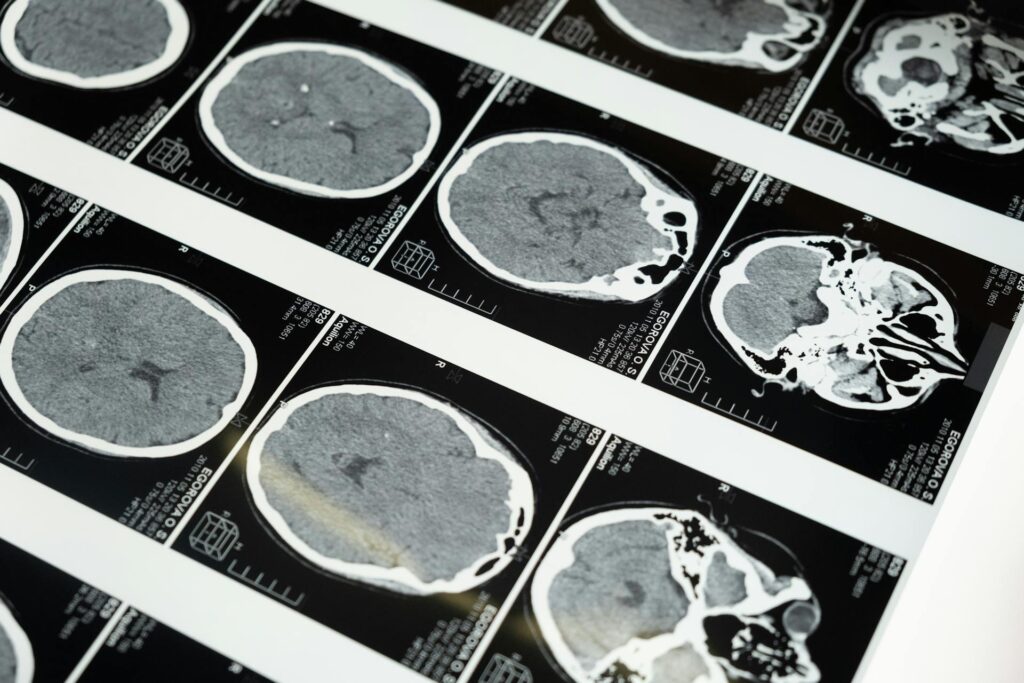

Traumatic brain injuries (TBIs) are injuries one can sustain following a violent blow or jolt to the head. In some instances, this can also result from a penetrating wound, like a bullet, traveling through the brain. Generally, when your brain sustains serious trauma, it can cause damage to the brain and ultimately impact the function of the organ.

Most commonly, this results in a concussion. When you are struck in the head or hit your head on a hard surface, the force of the impact can cause your brain to move inside your skull, often violently colliding with the interior wall of the skull. This can damage brain cells, impacting different aspects of your brain, like memory, thought process, and emotional regulation. Concussions can range in severity from mild to severe. In some instances, those who sustain a severe TBI or who have suffered multiple TBIs over the course of their life can suffer long-term impacts, like issues with balance, difficulty concentrating, and even an increased risk of developing a degenerative disease.